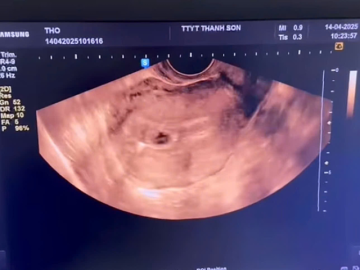

Trên thực tế, việc vòng tránh thai bị tuột ra ngoài hay lệch khỏi vị trí ban đầu không phải hiện tượng hiếm. Theo bác sĩ Nguyễn Thị Loan, phụ trách Phòng khám sản - phụ khoa Hồng Loan (Hà Đông, Hà Nội) cho biết, trường hợp tuột vòng tránh thai thường xảy ra trong 3 tháng đầu đặt vòng và nhất là trong chu kỳ kinh nguyệt. Một số chị em làm việc nặng, mang vác nhiều đồ cũng dễ khiến vòng tránh thai bị áp lực đẩy xuống thấp và tăng nguy cơ rơi ra ngoài.

Theo bác sĩ Loan, sau khi đặt vòng tránh thai, chị em nên nghỉ ngơi và tránh làm việc nặng (bê đồ nặng, tập thể thao, lên xuống cầu thang...) và cũng nên hạn chế quan hệ tình dục để vòng tránh thai được ổn định trong buồng tử cung. Bác sĩ Loan cho biết thêm, dấu hiệu để nhận biết vòng đã bị tuột ra ngoài hoặc lệch khỏi vị trí thường là rong huyết và đau bụng dưới. Tuy nhiên, một số trường hợp lại không để lại bất kỳ triệu chứng nào khiến chị em khó có thể nhận biết. Vì vậy, để đảm bảo an toàn, chị em cần đi kiểm tra định kỳ để xác định vị trí của chiếc vòng tránh thai.